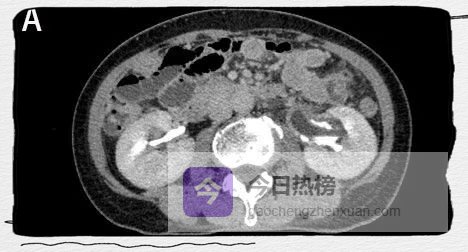

图2A

CT增强扫描呈双环及双腔改变,早期可见外腔密度增高。